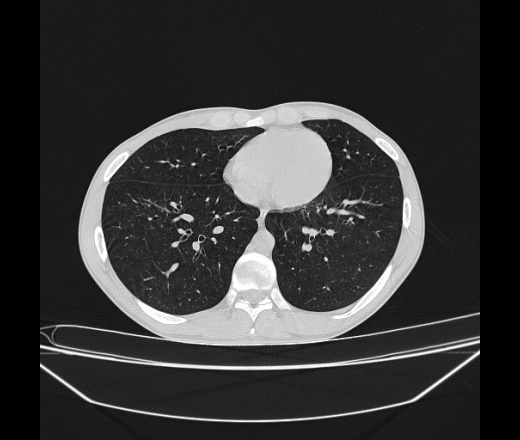

Молодой парень 18 лет, призывник, при прохождении ФЛС на верхушек левого легкого выявили очаги средней интснисвности с нечеткими контурами, тяжи. Сделали бок и томограммы 6-7-8. Везде описывают как очаговый твс. Вижу только перибронхиальный фиброз. Что за изменения в бронхах, указано нижи стрелками, тоже перибронхиальный?

Не стал бы говорить об очагах. Акцентировал бы не на фиброзе, а на тракционных бронхоэктазах. Не обязательно они результат tbc бронхов, но проверить не помешает.

Иван, пациент ведь уже "направлен с ОПТД", так?surprise Возвращайте его назад с заключением о возможном микобактериозе. Остаточные поствоспалительные ( посттуберкулёзные?) в дифряд.Очаговый твс с неясной активностью они уже себе "нарисовали", как я поняла.

+1 за микобактериоз.